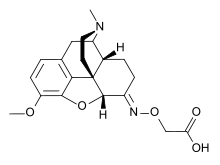

- Semi-synthetic opioids: created from either the natural opiates or morphine esters, such as hydromorphone, hydrocodone, oxycodone, oxymorphone, ethylmorphine and buprenorphine;

- Naloxegol (Naloxegol is only peripherally active as it does not cross the blood–brain barrier in sufficient quantities to be centrally active. As such, it can be considered the antitheses of loperamide.)